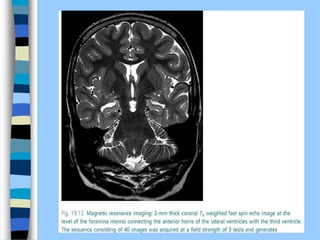

 Magnetic resonance imaging (MRI): basic principles of

NMR can be applied to imaging of live samples. (MRI) can be

applied to large volumes in whole living organisms and has a

central role in routine clinical imaging of large-volume soft

tissues.